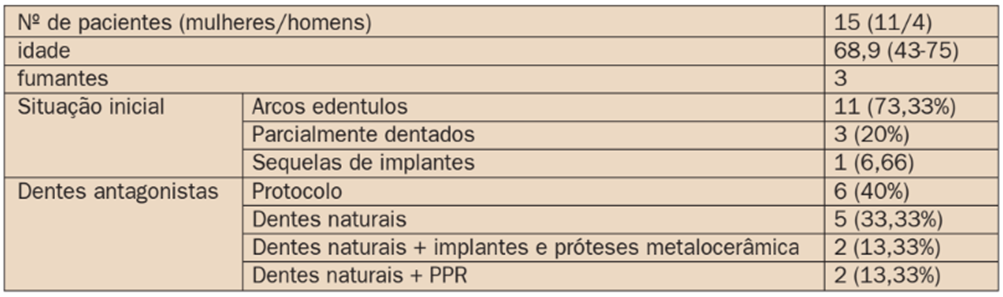

Quinze pacientes consecutivos, sendo 11 mulherese quatro homens, com idade media de 68,9 anos foram tratados pela técnica all-on-four standard em carga imediata com implantes Maestro (Implacil De Bortoli / São Paulo / Brasil). A tabela 1 descreve os pacientes pela situação clínica inicial e a situação da arcada antagonista.

A tabela 2 apresenta os dados referentes aos implantes utilizados e a angulação dos componentes protéticos. Os implantes de 15 mm de comprimento foram os mais utilizados (36,66%), enquanto que implantes de 9 mm foram os menos utilizados, correspondendo a apenas 3,33% das fixações utilizadas. Os componentes de 17º foram os mais utilizados (58,33%), principalmente para corrigir a inclinação dos implantes distais.

Alguns implantes precisaram de implantes de 30º (6,66%) em virtude da maior inclinação dos implantes distais. Os componentes retos foram utilizados nos implantes anteriores. Alguns destes implantes anteriores também precisaram de componentes angulados, muitas vezes em virtude da discrepância entre os maxilares.

TABELA 1: Descrição dos pacientes quanto ao gênero, idade, uso de cigarros, condição inicial da maxila e da mandíbula quanto a situação dentária: